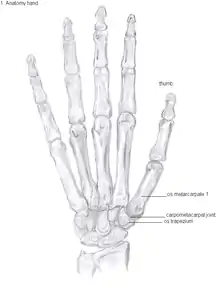

Anatomy

The TMC joint is a synovial joint between the trapezium bone of the wrist and the metacarpal bone at the base of the thumb. This joint is a so-called saddle joint (articulatio sellaris), unlike the CMC joints of the other four fingers which are ellipsoid joints.[17] This means that the surfaces of the TMC joint are both concave and convex.